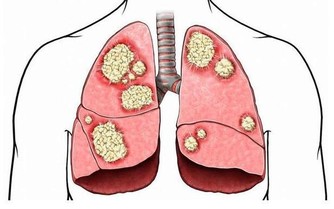

血管就像軟水管,好的水管內壁,應該光滑通暢。

如果將好血管和“生了病”的血管放在你面前,你會發現,

好的血管看上去特別舒服,動脈血管富有活力,管壁十分光滑,看不到什麼雜質,這种血管輸送血液的能力也最強。

但“生了病”的血管,其管道內壁就被各種“垃圾”佔據,形成如同黃色小米粥樣的斑塊,

久而久之血液流動受阻,最終因缺血引發多種疾病。